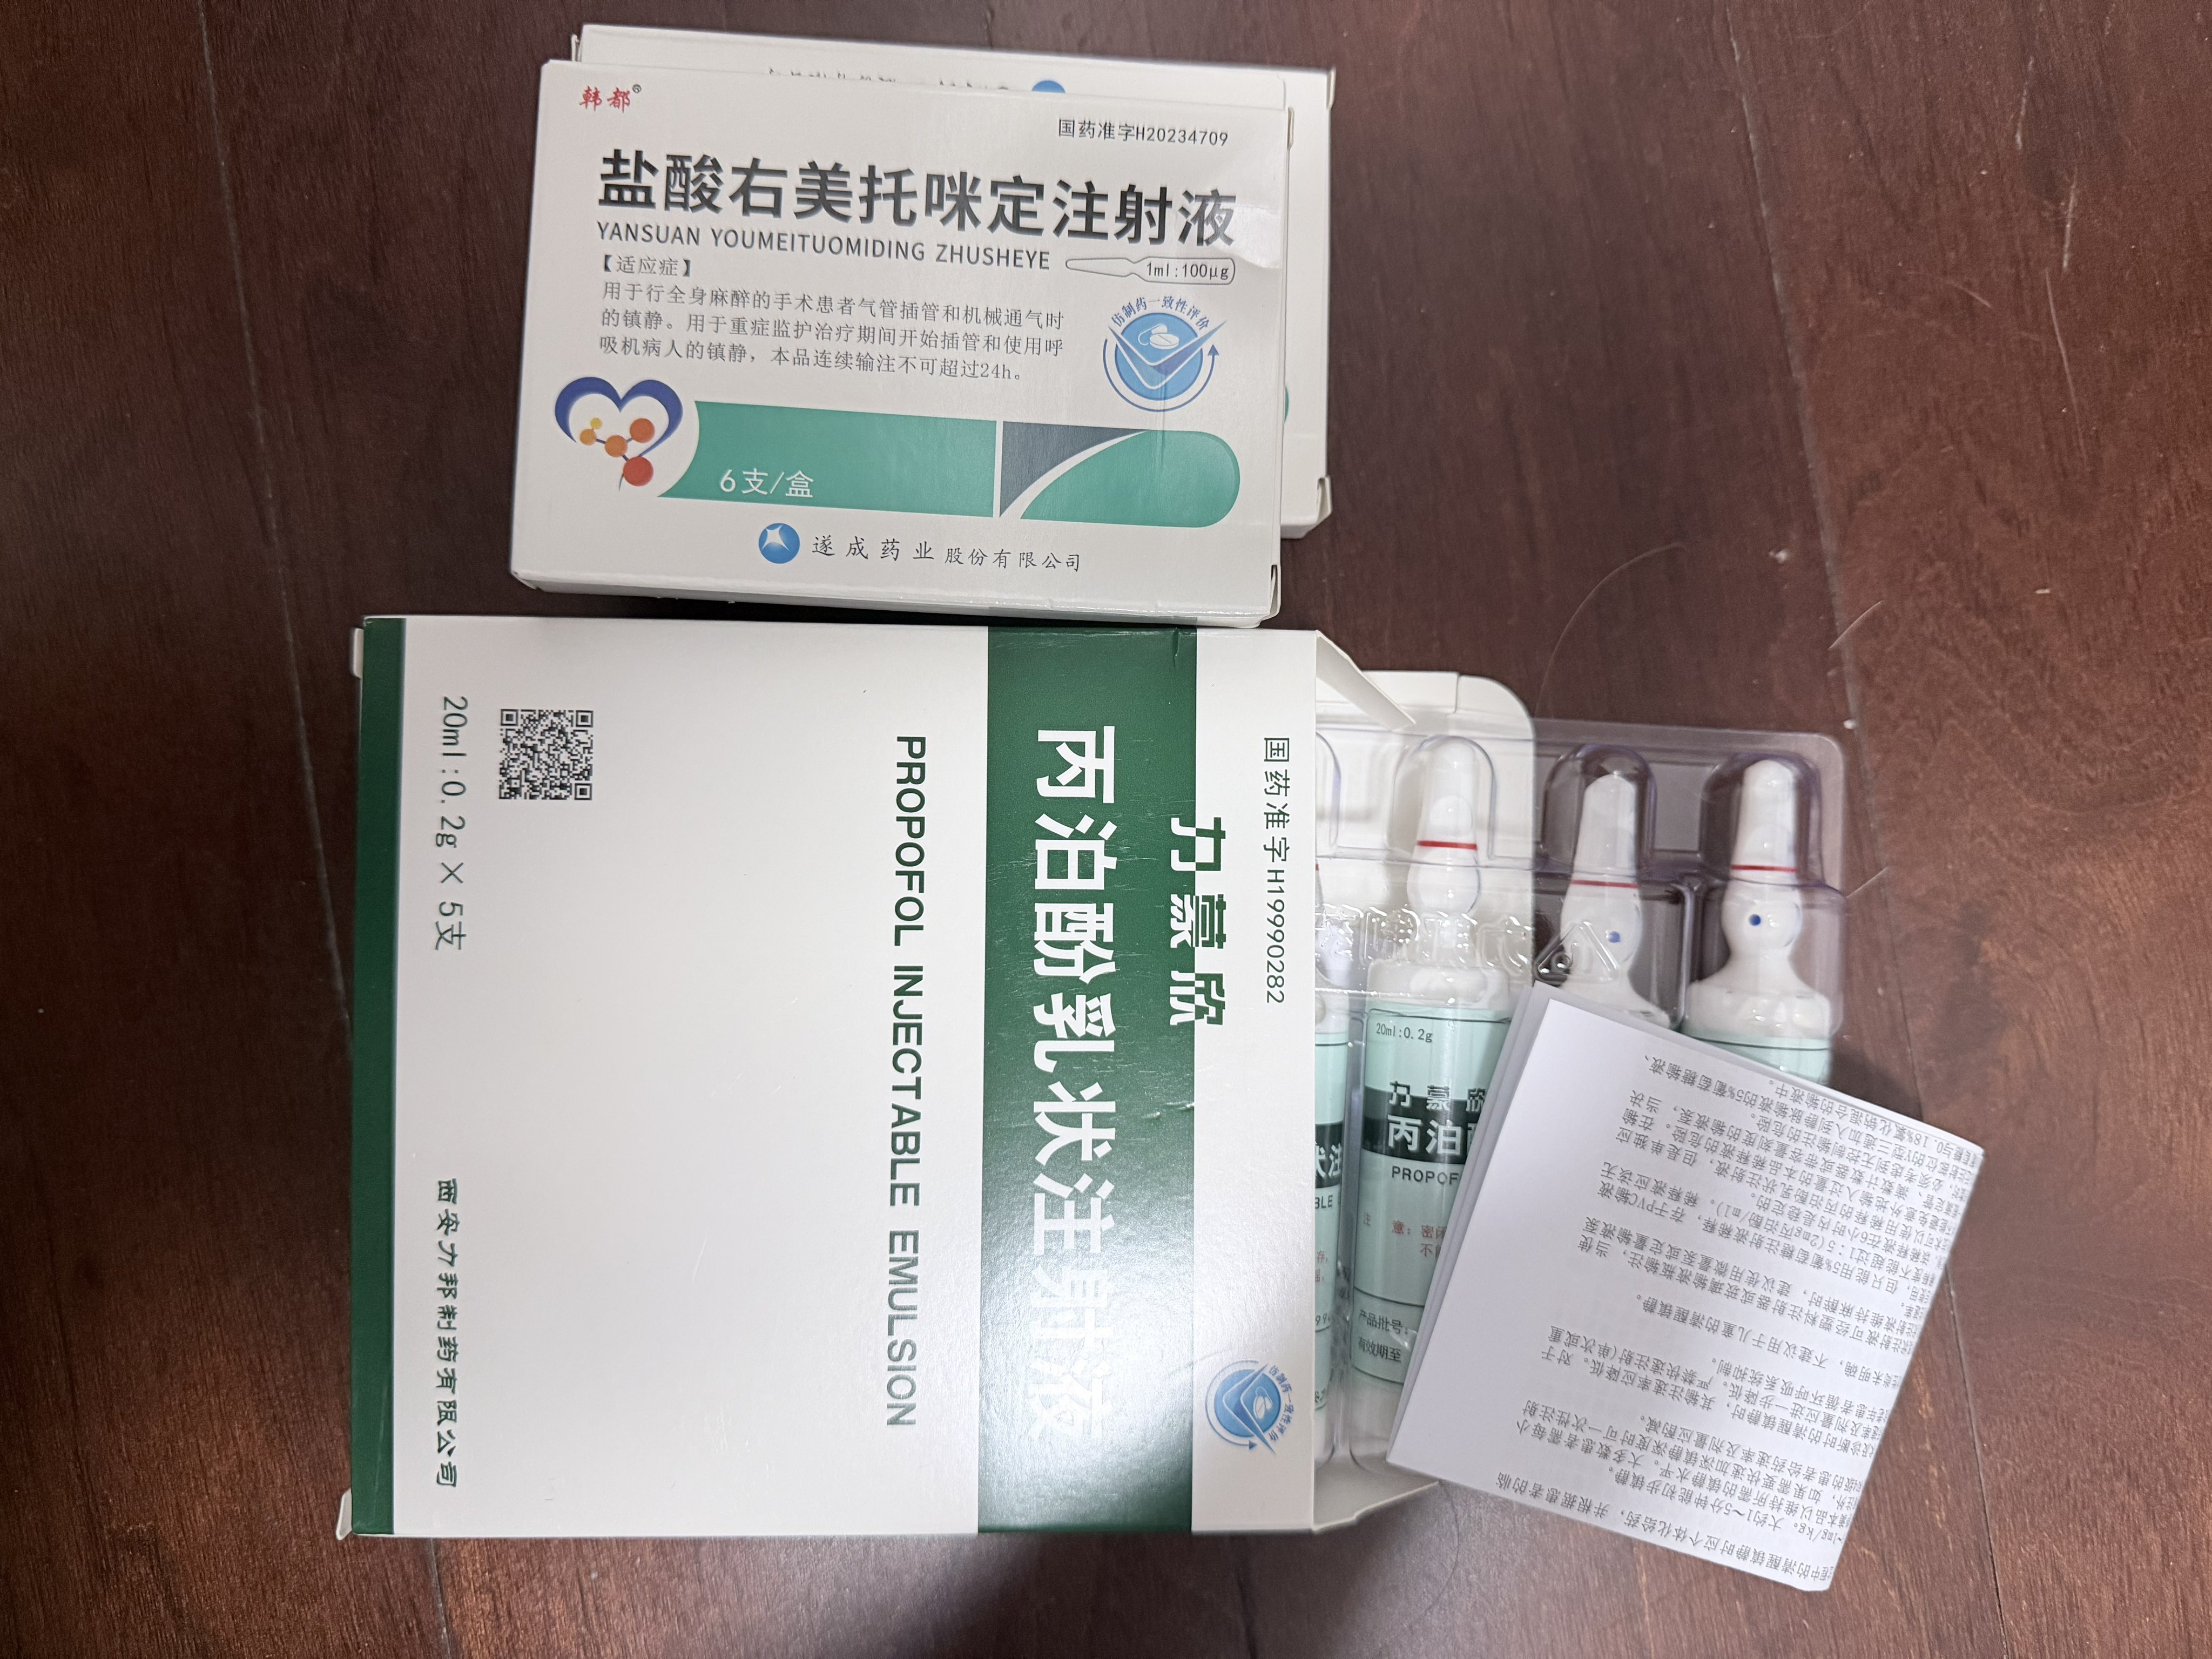

而临床处理药物中毒中,其实医生更常用的做法是保守、支持性的治疗,比如补液,促进代谢,必要时镇静,以及监测生命体征防治并发症。

而临床处理药物中毒中,其实医生更常用的做法是保守、支持性的治疗,比如补液,促进代谢,必要时镇静,以及检测生命体征防治并发症。

对于药物过量引起的中枢神经系统副作用,有一些不常见或常见的药物来控制症状。